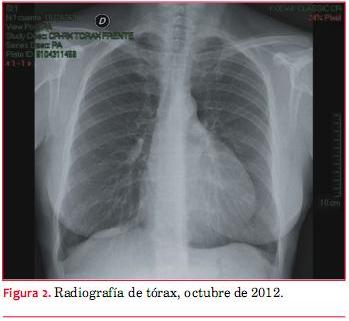

La paciente aporta otra radiografía realizada 18 meses antes (figura 2) en la que la silueta cardíaca también estaba aumentada, con un aspecto más globuloso, pero en una magnitud mucho menor a la observada en el momento de la consulta. En ambas radiografías se sospecha una masa ovoidea de distinta densidad, sobreimpuesta al borde izquierdo de la verdadera silueta del corazón.

Hemos presentado el caso de una paciente asintomática con el hallazgo de un marcado incremento de la silueta cardíaca en una radiografía de tórax. El ecocardiograma mostró una extensa colección líquida paracardíaca y la tomografía de tórax mostró un voluminoso quiste de mediastino anterior, que se extendía desde encima del cayado aórtico hasta la proximidad del ángulo costo-frénico izquierdo.